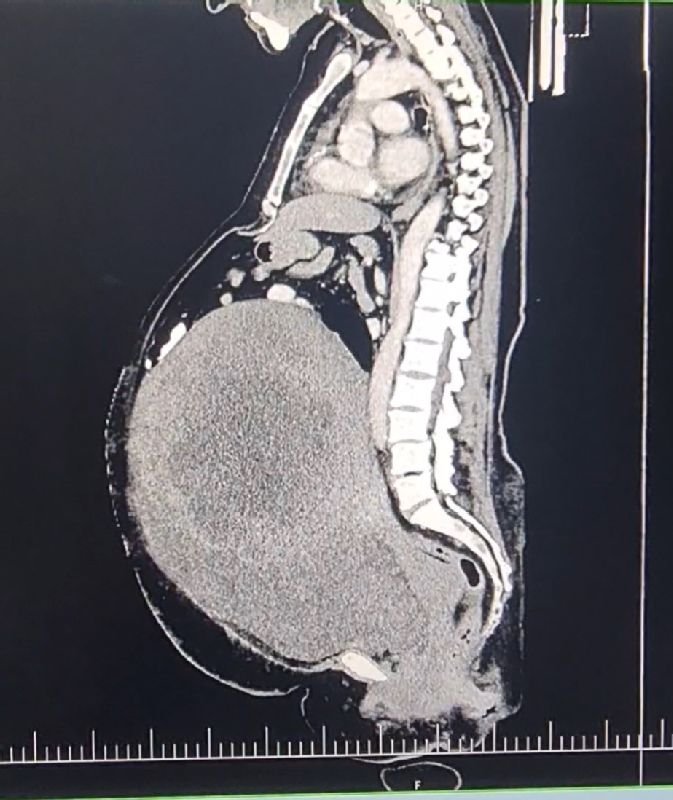

Galéria k článku Neuveriteľný ÚSPECH: V Komárne žene vyoperovali OBROVSKÝ nádor! Vážil 18 KÍL

Zdroj: Nemocnica AGEL Komárno